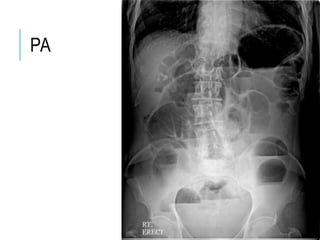

ABDOMINAL X-

RAY

AP

PA

GAS UNDER DIAPHRAGM